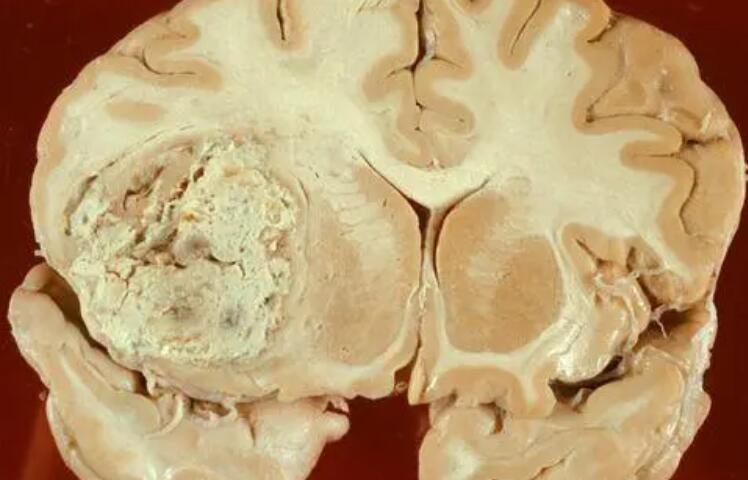

背景:GBM治疗的挑战与需求

胶质母细胞瘤是一种高度侵袭性的脑肿瘤,传统治疗方法效果有限,因此寻找更有效的治疗手段一直是医学界迫切的需求。olaptesed pegol作为CXCL12抑制剂,与VEGF抑制剂贝伐珠单抗和放疗的联合治疗显示出了显著的潜在生存优势。